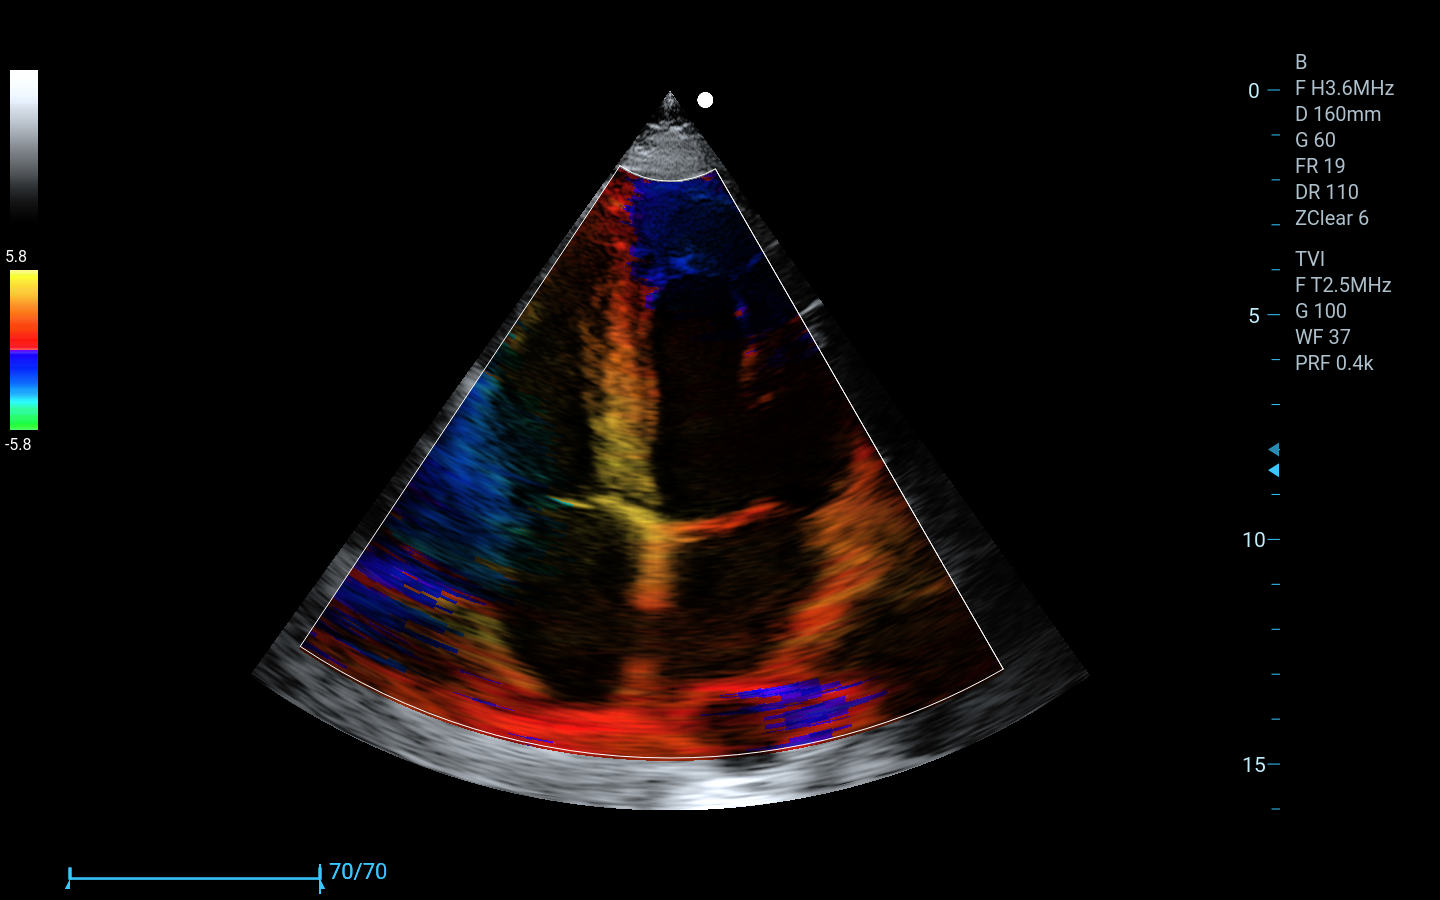

Cardiología

Phased Array (cardiología)

Color Doppler (CDFI), Power Doppler (PDI/DPDI)

TDI (TVI, TVD, TVM, TEI)

Imágenes clínicas extraordinarias